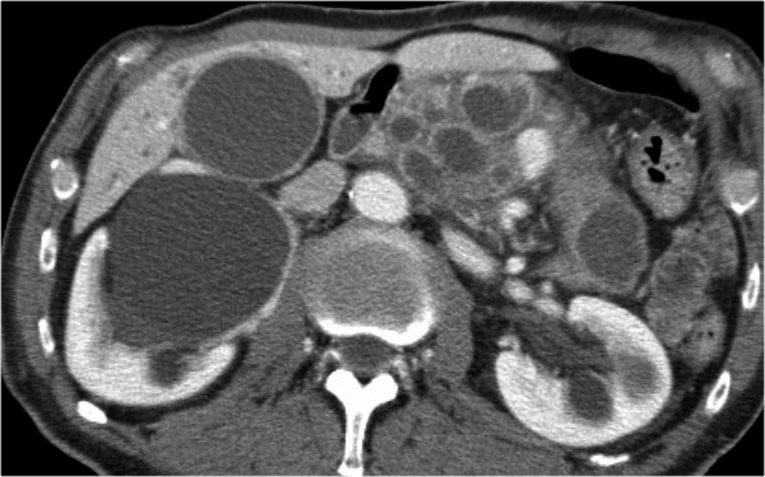

CT cho thấy hai nang lớn ở bệnh nhân nữ 45 tuổi có tiền sử chấn thương (hình).

Lưu ý hình ảnh thâm nhiễm mỡ trong khoang sau phúc mạc (mũi tên).

Kết hợp đặc điểm hình ảnh với tiền sử lâm sàng, rất có khả năng đây là các nang giả tụy do chấn thương.